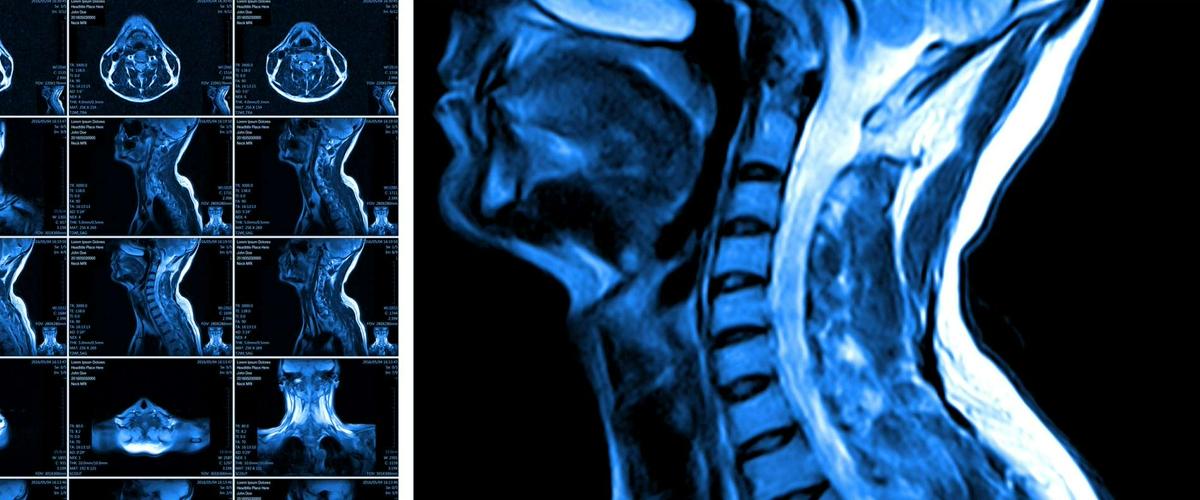

Спинной мозг передает сигналы от головного мозга к остальным частям тела, однако травмы спинного мозга часто приводят человека к полному или частичному параличу. Это происходит из-за повреждений нервных волокон и главную роль в этом процессе играет потеря олигодендроцитов — клеток, которые участвуют в передаче сигналов нейронов.

Обычно поврежденные ткани организма можно восстановить с помощью стволовых клеток, которые восполняют запасы утраченных. В спинном мозге эта возможность ограничена, поскольку после травмы они, в основном, образуют рубцы. Это ограничивает степень повреждения, но не способствует восстановлению потерянных клеток.

Контролируя активированные гены в стволовых клетках, ученые смогли стимулировать выработку новых олигодендроцитов, что привело к улучшению функции нервных волокон в поврежденном спинном мозге мышей.

Это означает, что на стволовые клетки нервной системы можно воздействовать для функционального восстановления, заключили авторы. Дальнейшие исследования должны подтвердить потенциал этой терапевтической стратегии для человека. Это дает новую надежду на появление терапии для обездвиженных пациентов, которые из-за травмы спинного мозга остаются прикованными к инвалидным креслам.